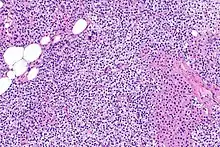

Primary hyperplasia of the parathyroid gland, results from both hypocalcaemia and increased phosphate levels by decreasing expression of calcium sensing receptors and vitamin D receptors at the parathyroid gland.[8][4] These decreases in receptor expression lead to hyperfunctioning of the parathyroid. Hyperfunction of the parathyroid gland is thought to exacerbate primary hyperplasia which evolves further to a secondary more aggressive hyperplasia. Histologically, these hyperplasic glands can be either diffuse or nodular.[24] Primary hyperplasia, usually resulting in diffuse polyclonal growth is manly related to reversible secondary hyperparathyroidism. Secondary hyperplasia of the parathyroid gland is more often a nodular, monoclonal growth that sustains secondary hyperparathyroidism and is the catalyst in the progression to tertiary hyperparathyroidism. Nodular hyperplastic glands in tertiary hyperparathyroidism are distinctly larger in both absolute size and weight up to 20-40-fold increases have been reported.[25][26][24]

Parathyroid glands are normally composed of chief cells, adipocytes and scattered oxyphil cells.[27][14] Chief cells are thought to be responsible for the production, storage and secretion of parathyroid hormone. These cells appear light and dark with a prominent Golgi body and endoplasmic reticulum. In electron micrographs, secretory vesicles can be seen in and around the Golgi and at the cell membrane. These cells also contain prominent cytoplasmic adipose.[27][14] Upon onset of hyperplasia these cells are described as having a nodular pattern with enlargement of protein synthesis machinery such as the endoplasmic reticulum and Golgi. Increased secretory vesicles are seen and decreased intercellular fat is characteristic.[27][24] Oxyphil cells also appear hyperplasic however, these cells are much less prominent.

Biochemically, there are changes in function between normal and nodular hyperplastic parathyroid glands. These changes involve proto-oncogene expression and activation of proliferative pathways while inactivating apoptotic pathways.[28] In nodular parathyroid tissue increased expression of TGF-a, a growth factor, and EGFR, its receptor, results in aggressive proliferation and further downregulation of vitamin D receptors, which act to suppress hormone secretions.[25][8][28] Furthermore, the proliferative marker, Ki67 is seen to be highly expressed in the secondary nodular hyperplastic state.[28][25] Tumour suppressor genes have also been highlighted as being silenced or degraded in nodular hyperplastic parathyroid tissue.[8][28] One such gene, p53, has been shown to regulate multiple tumour suppressor pathways and in tumorigenesis can be degraded by b-catenin. This pathway, in some aspect, is mediated by CACYBP, which is highly expressed in nodular parathyroid hyperplasia.[28]